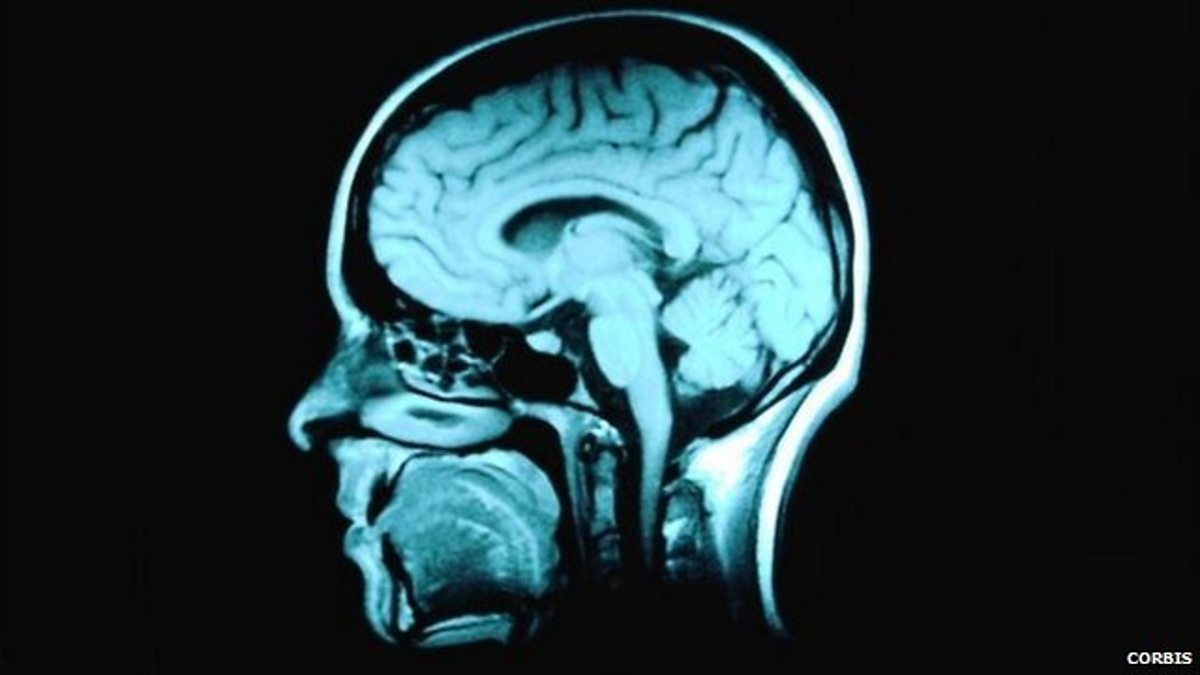

'Deep learning' technology inspired by human brain

The BBC's science reporter Rebecca Morelle discovers the benefits of 'deep learning'.